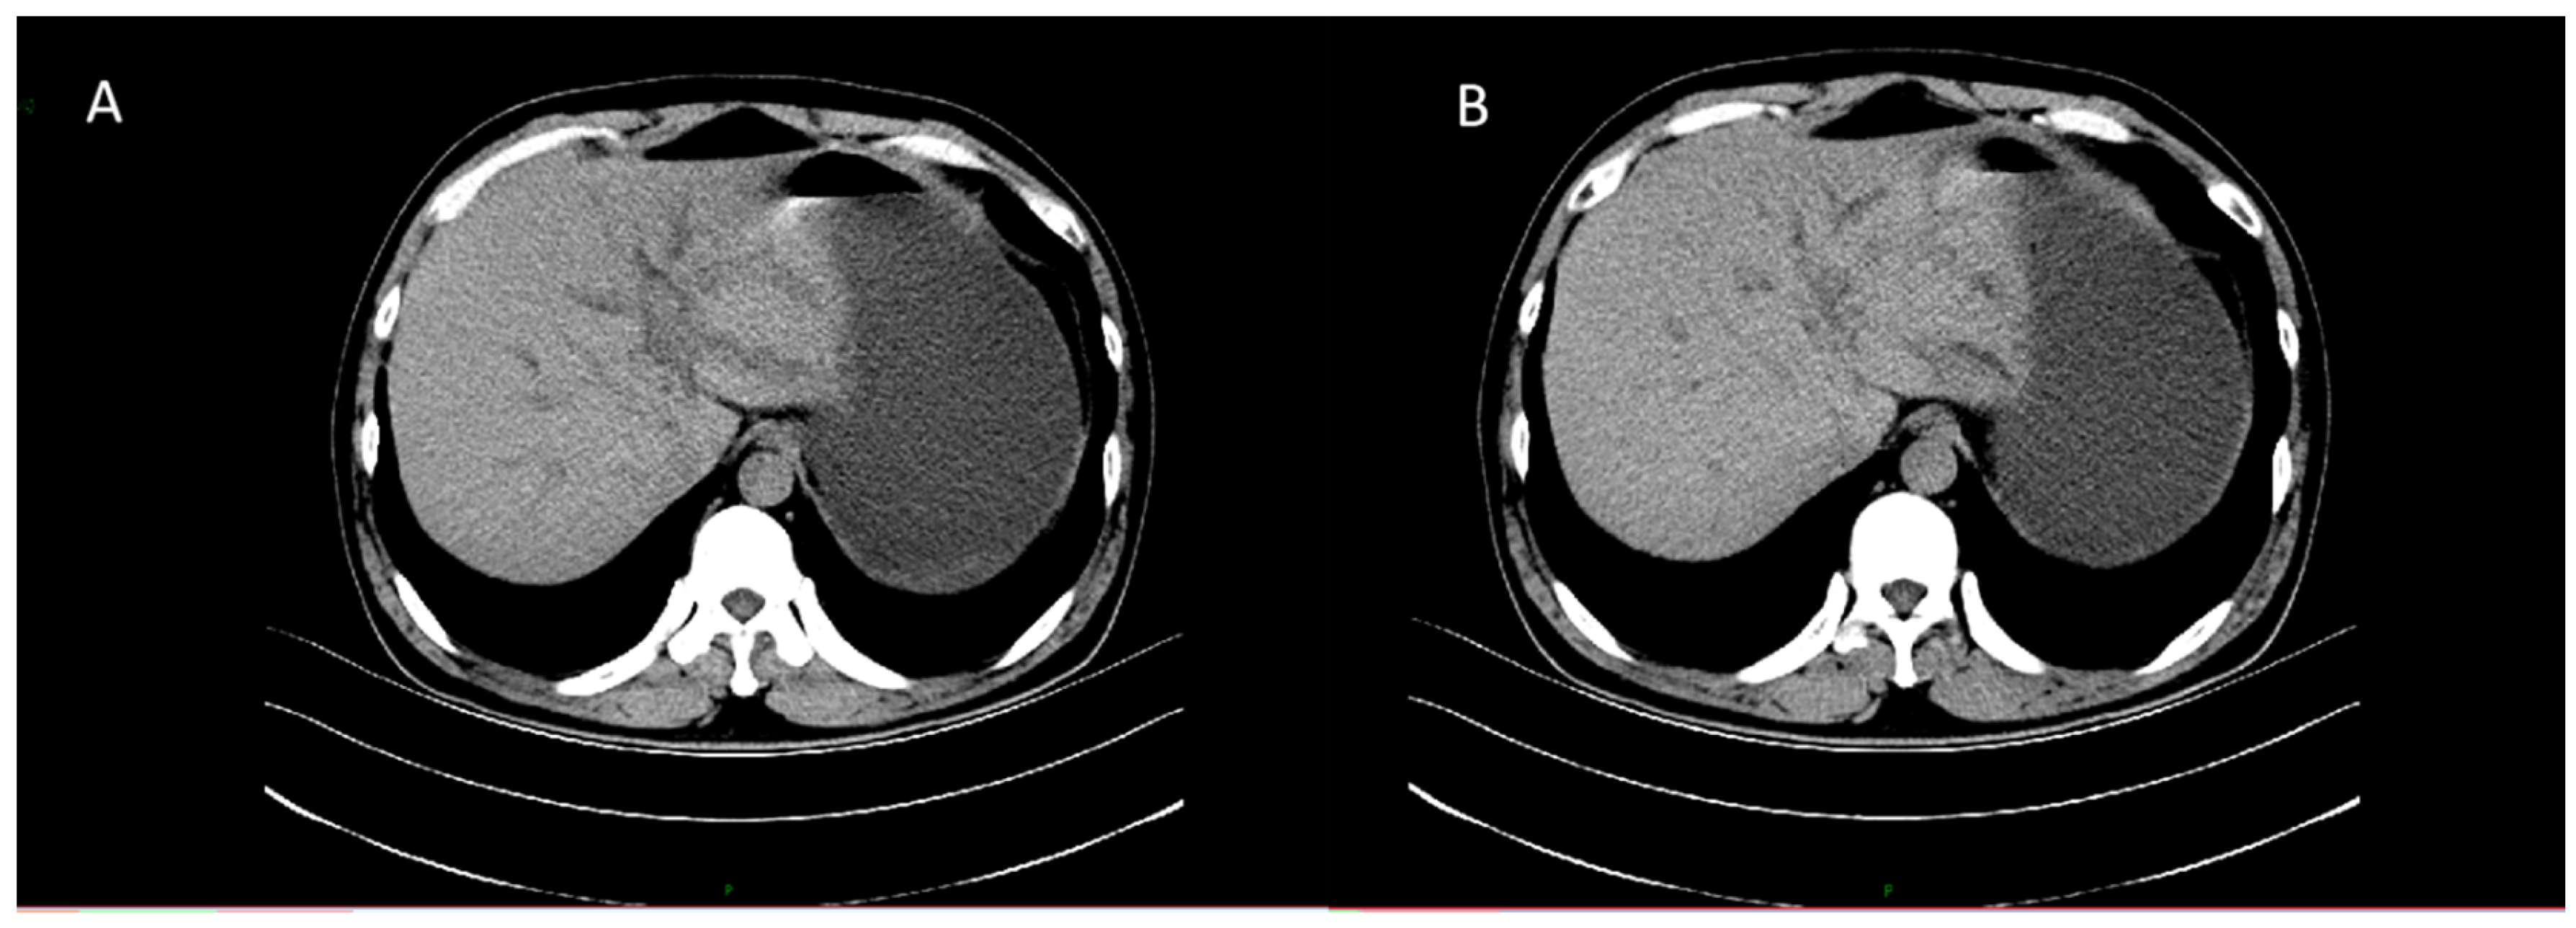

MRI showed a mass-like lesion in the left hepatic hilum, about 30 × 22 mm, with ill-defined borders and marked enhancement after contrast. Dilatation of intrahepatic bile ducts and multiple enlarged lymph nodes in the hepatic hilum were also observed (Figure 2).

The left hepatic lobe near the hilum shows a mass-like lesion with slightly high signal intensity on T2WI and mild perilesional edema.

Figure 2. Axial T2-weighted MR images of the liver. (A) Axial view demonstrating a well-defined hilar lesion with dilated intrahepatic bile ducts. (B) Coronal view showing the hepatic hilar mass with intrahepatic biliary dilatation and gallbladder distension.